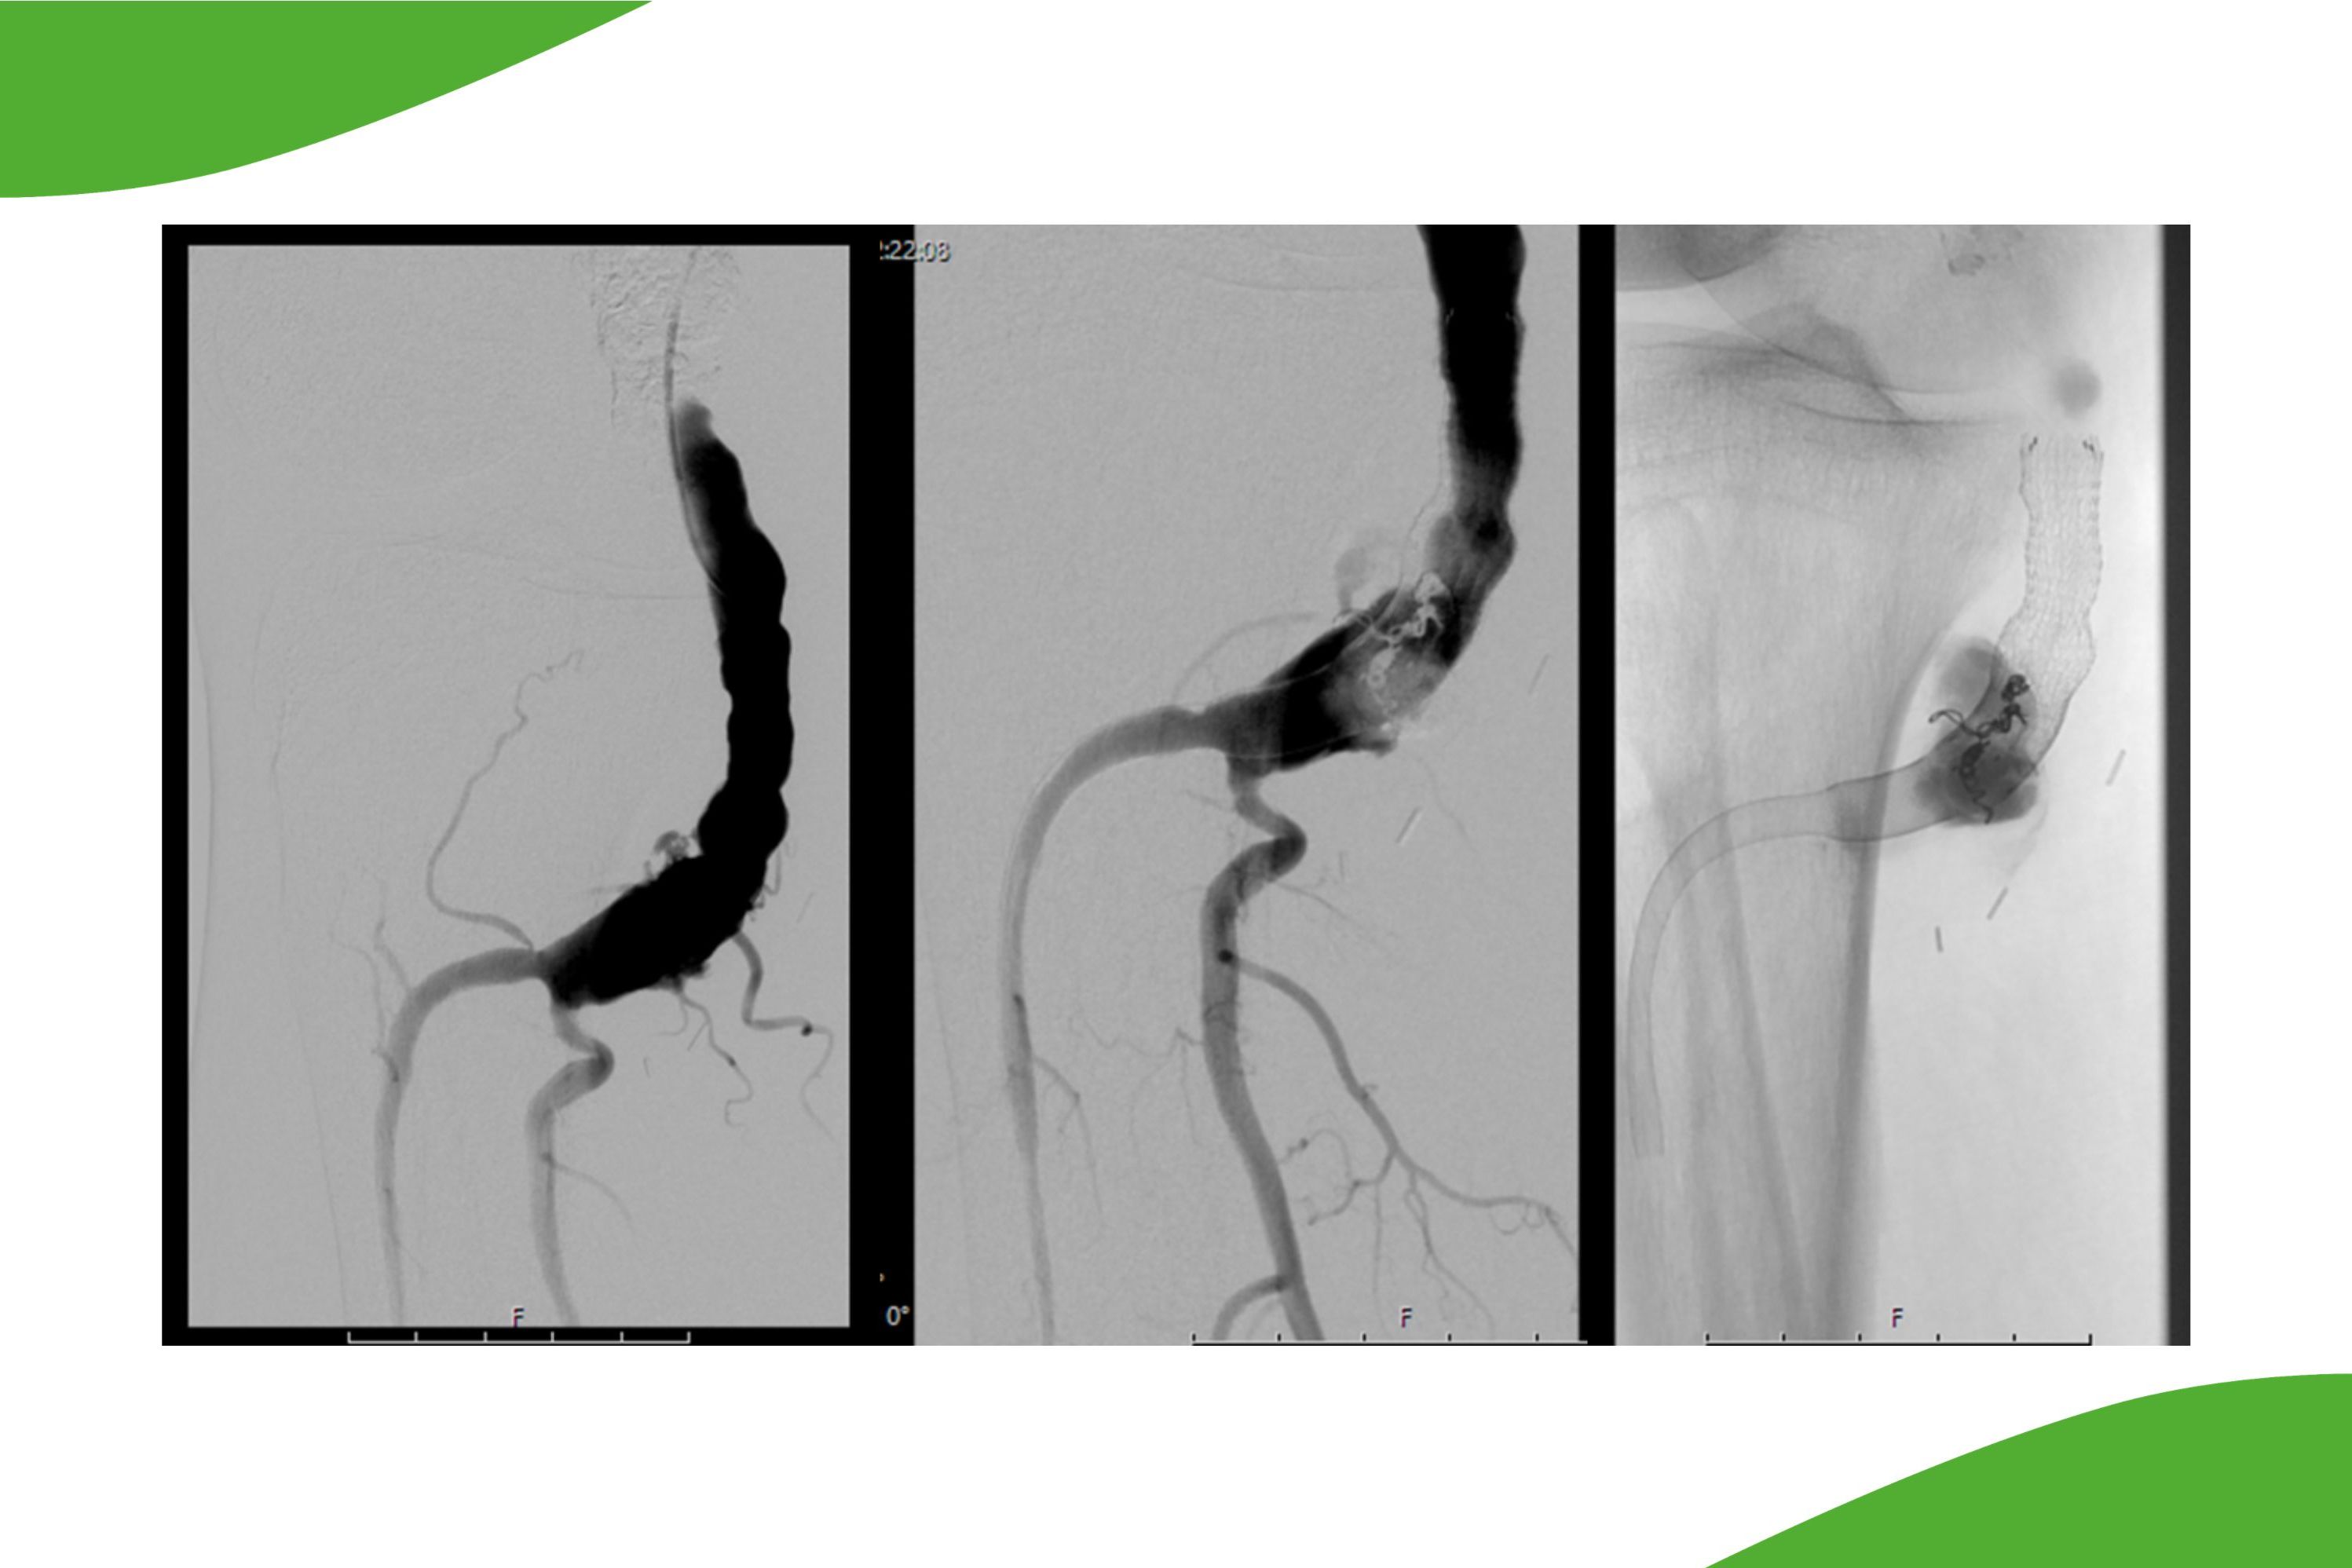

Angiographie der Bauchschlagader – wann wird untersucht und behandelt?

Bei Aneurysma:

Liegt eine Aussackung der Aorta (Bauchschlagader) vor, spricht der Mediziner von einem Aneurysma. Dieses kann verkalken oder Blutgerinnsel enthalten. Die sogenannten Thromben können in kleinere Gefäße gelangen und zu Verschlüssen führen. Eine weitere Komplikation ist die Ruptur des Aneurysmas (Platzen) mit der Gefahr eines lebensbedrohlichen Blutverlustes.

Neben der offenen OP können viele Aneurysmen auch mit ummantelten Stents (sogenannte Aortenstentgrafts) versorgt werden, wobei auch komplexere Eingriffe mit individuell angepassten Prothesen und Seitenärmchen durchgeführt werden. Welches Verfahren eingesetzt werden kann, wird interdisziplinär im Gefäßzentrum des Klinikum Saarbrücken besprochen.

Das Gefäßzentrum am Klinikum Saarbrücken ist eines der wenigen Zentren, welches alle enodovaskulären Verfahren zur Versorgung von Aneurysmen distal des Aortenbogens anbieten kann. Darüber hinaus werden auch aus einem überregionalen Einzugsgebiet ggf. erforderliche Folgeeingriffe nach Aortenstentgraft (EVAR-Repair) durchgeführt (siehe Spezialverfahren und neue Behandlungsmethoden).